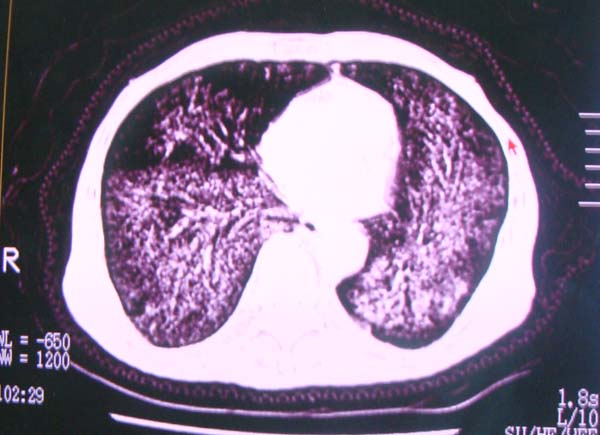

以下是引用zhangzhongshou在2008-2-15 22:25:00的发言:[br]片子照得不清,基本考虑1、细支气管肺泡癌2、亚急性血行播散型肺结核。请结合临床。片子细节显示不清,无法提供进一步意见。

以下是引用杀毒软件在2008-2-15 22:34:00的发言:[br]小叶中心性肺气肿。两肺弥漫性病变,肺泡微石病,过敏性肺炎,尘肺2期,特发性肺纤维化都有可能。[br]不象肺泡癌。